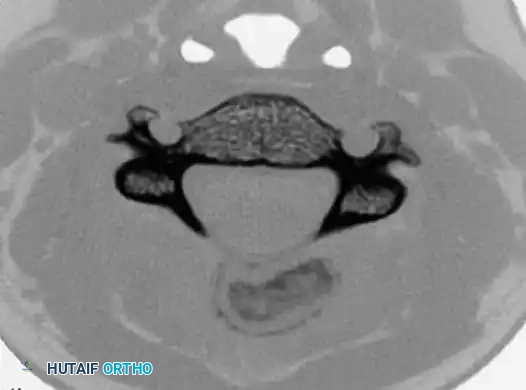

Axial and sagittal CT scans clearly defining the expansile, mineralized matrix of the osteoblastoma within the posterior elements, allowing for precise surgical planning.